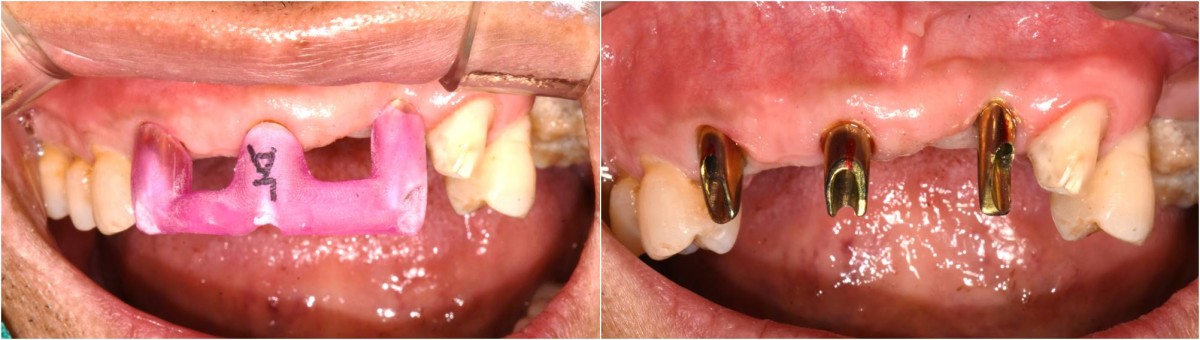

<GCpbc> A 58-year-old male is a patient undergoing implant installation in various parts. The old Br of the anterior maxilla has fallen

off and it is no longer possible to maintain it even temporarily, so a

treatment plan for the anterior teeth was made.